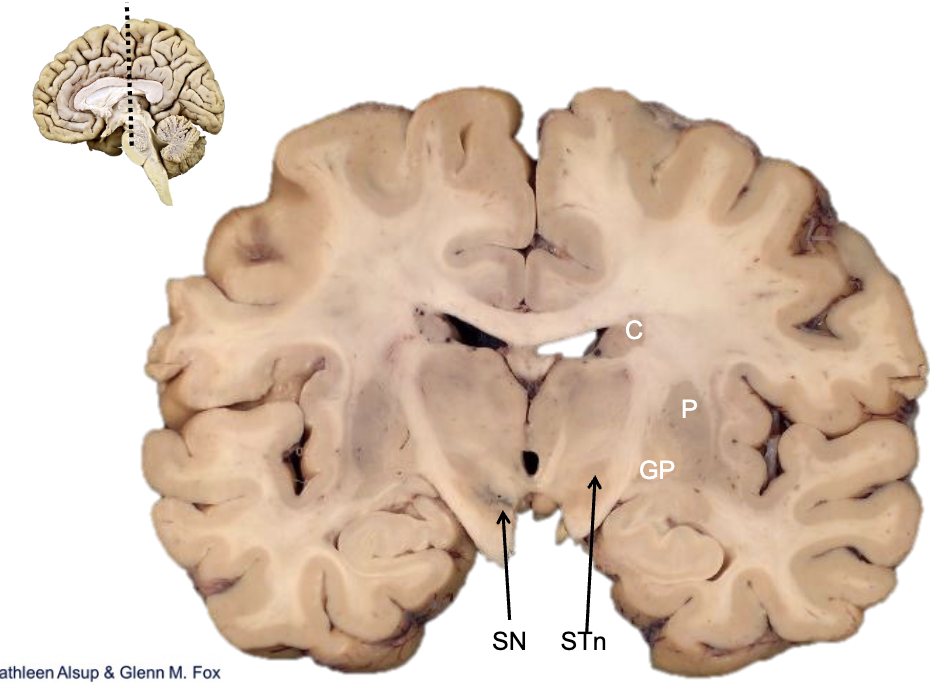

<p><strong>what is STn?</strong></p>

subthalamic nucleus

<p><strong>what is SN?</strong></p>

substantia nigra

<p><strong>what is gp?</strong></p>

globus pallidus

<p><strong>what is p?</strong></p>

putamen

<p><strong>what is c?</strong></p>

caudate